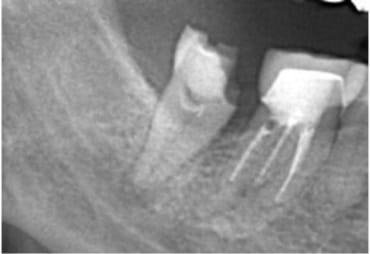

近所のかかりつけの歯科医院で、「再治療できないから奥歯を抜くしかない」と言われた。

あきらめきれず、HPで探して当院へ来院。

外すと中がドロドロに虫歯に感染していました。

折れて残っていた機具を除去

治療後病気がなくなり骨が再生した